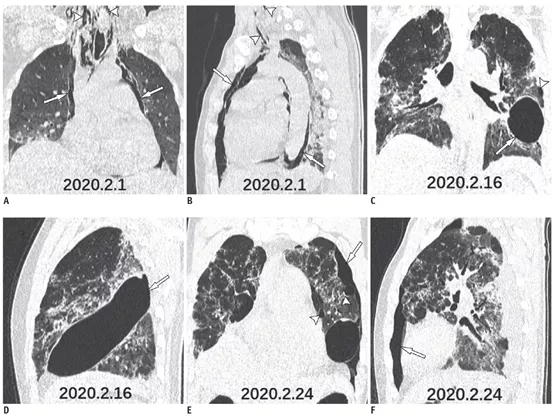

患者入院胸部CT提示左下肺叶毛玻璃影(图1A),在接下来的10天中,肺部病变的范围增加,并逐渐实变(图1B-D)。患者临床症状恶化,诊断为急性呼吸窘迫综合征,CT随访提示纵隔气肿(图1D,2A,B)。在支持治疗15天后,患者胸部CT提示肺部病变改善,纵隔气肿消失,左肺出现巨疱(图1E,F,2C,D)。八天后,CT提示左侧少量气胸和胸腔积液(图1F,2E,F)。

图2

在严重的COVID-19病例中,由于弥漫性肺泡损伤,更容易引起肺泡破裂,此外,剧烈咳嗽也可能引起肺泡破裂。纵隔肺气肿是由肺泡压力突然升高,引起肺泡破裂,气体进入肺间质,可发生在严重急性呼吸综合症。患者胸部CT发现胸膜下区域有多个肺大疱(图2C, E箭头),肺实变较对侧明显,易破裂引起气胸。